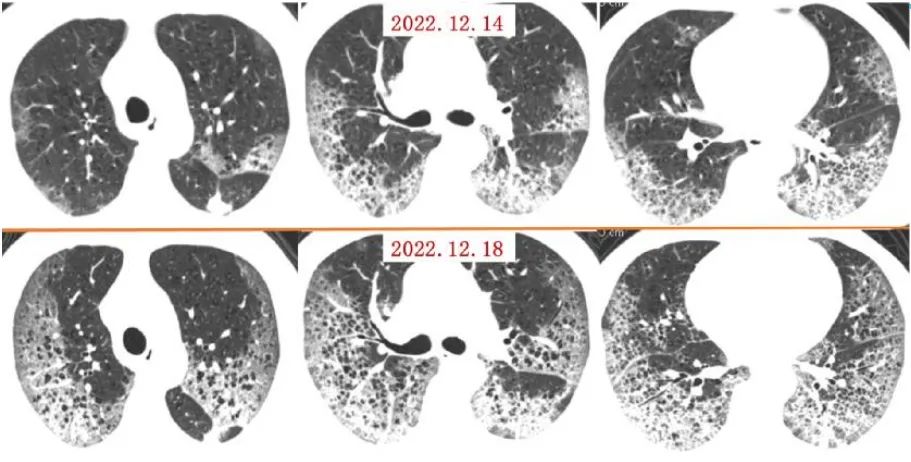

案例一,61歲,女性,確診病例

影像所見:有慢性阻塞性肺疾病病史。2周前受涼后出現(xiàn)發(fā)熱,伴咳嗽、咳痰。入院后給予吸氧,5天后出現(xiàn)口唇紫紺 ,改為BIPAP呼吸機輔助通氣。12月14日和12月18日,兩肺病灶自肺野外周、下后部向中心和上部迅速擴展,表現(xiàn)為“白肺”。